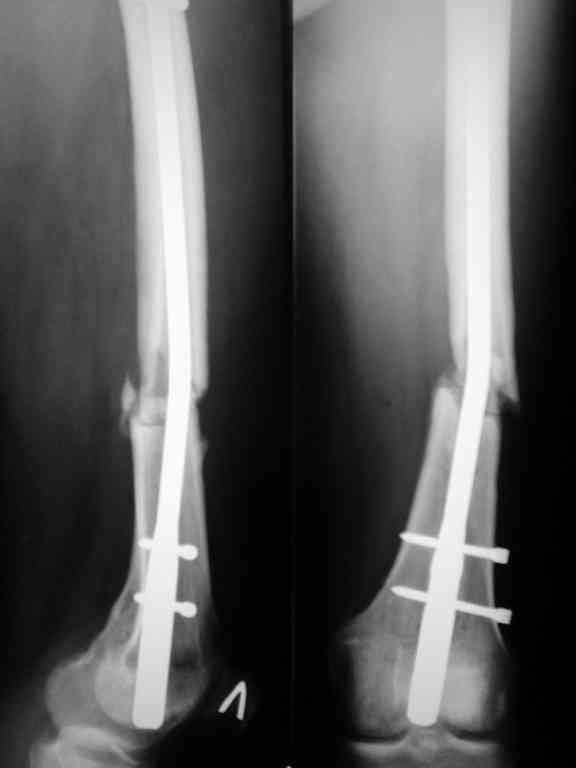

Уважаемый Александр. Случай достаточно интересный, поскольку за 2 года,почему то ничего не срастается и все ломается. Жаль нет рентгенограмм таза и голени.Основными причинами несращения переломов бывает 1.не правильно выбранная тактика лечения, в том числе тактика оперативного лечения ( к примеру - не тот фиксатор, не того размера, неправильно установлен и т.д.)2.Девитализация костных отломков, а судя по рентгенограммам старались вы на совесть, когда открывали область перелома при интрамедуллярном остеосинтезе. Кстати, если это был не блокируемый остеосинтез, а обычный, то понятно почему стержень согнулся и нет сращения. На представленных рентгенограммах отдельные винты расположены даже с внутренней стороны, т.е. открылись вы качественно. 3.не правильно выбранная тактика лечения в п.операционном периоде или не выполнения больным данных рекомендаций. По бедру - мы бы убрали пластину и выполнили ретроградный блокируемый остеосинтез с рассверливанием. Если нет возможности, есть аппарат Илизарова. Но мороки и для вас и для больного много.

1. Рентгенограммы обязательно дошлю.

2. "судя по рентгенограммам старались вы на совесть, когда открывали область перелома при интрамедуллярном остеосинтезе"

? - но как это можно определить по снимкам, да еще и выполненным через 20 месяцев после первичной операции)

При первичном интрамедуллярном остеосинтезе применялся блокируемый гвоздь диаметром 9 мм ретроградно. У пациентки узкий костномозговой канал, поэтому были сложности (рассверливали долговато). Что касается разреза то его длина была 3-4 см не более. Т.е. насчет девитализации я согласен, но именно за счет рассверливания.

Винты с внутренней стороны кости фиксируют трансплантат, взятый из гребня подвздошной кости. Он довольно массивный и был уложен в дефект по передне-медиальной поверхности кости. тут уж пришлось действительно открываться на совесть.

В приложении рентгенограмма бедра за авгутст 2005 с согнутым гвоздем и первичные.